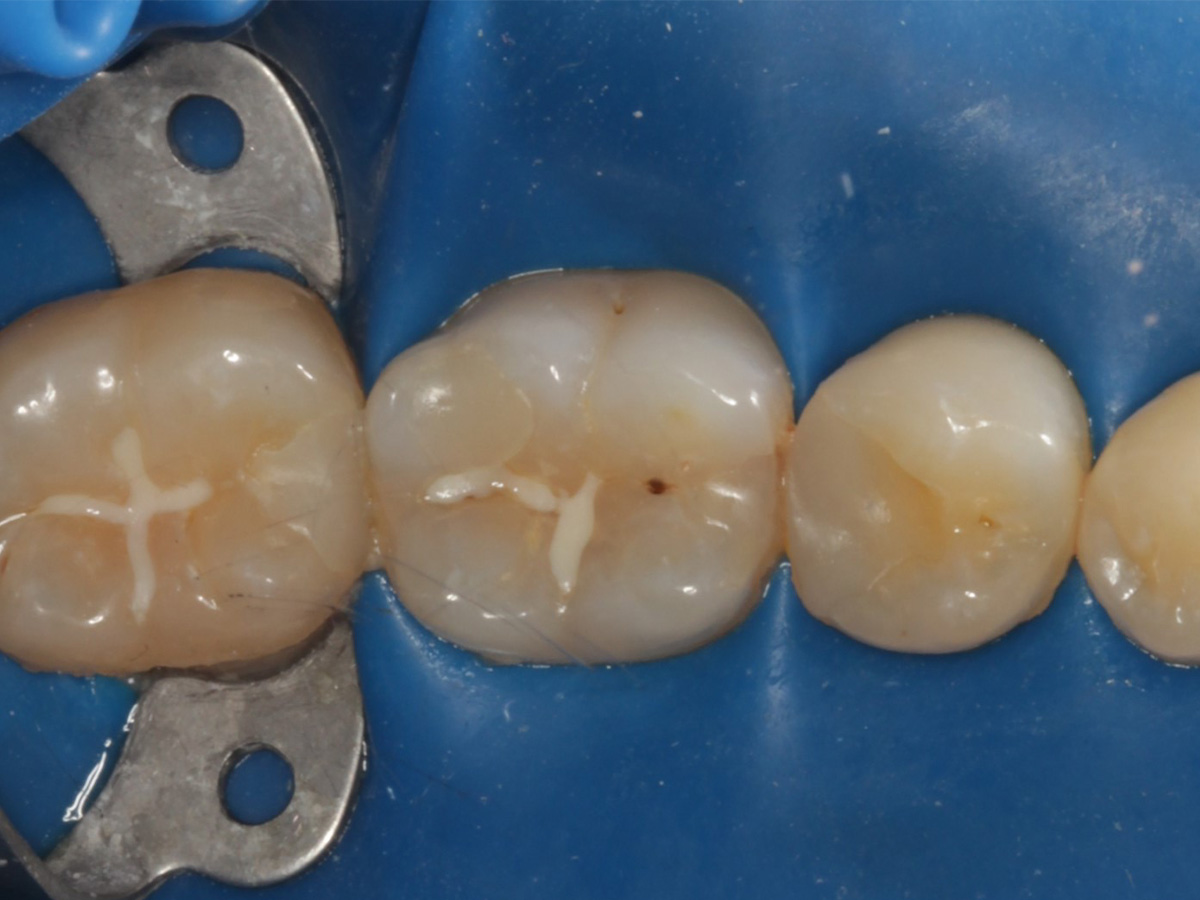

Abbildung 22

Fertige Restauration Zahn 46